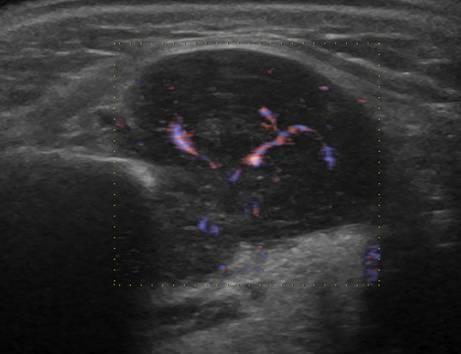

УЗИ лимфоузлов при лимфоме Ходжкина